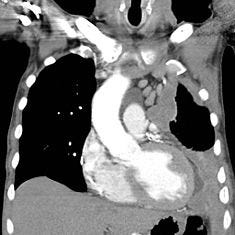

(image: Wikipedia)